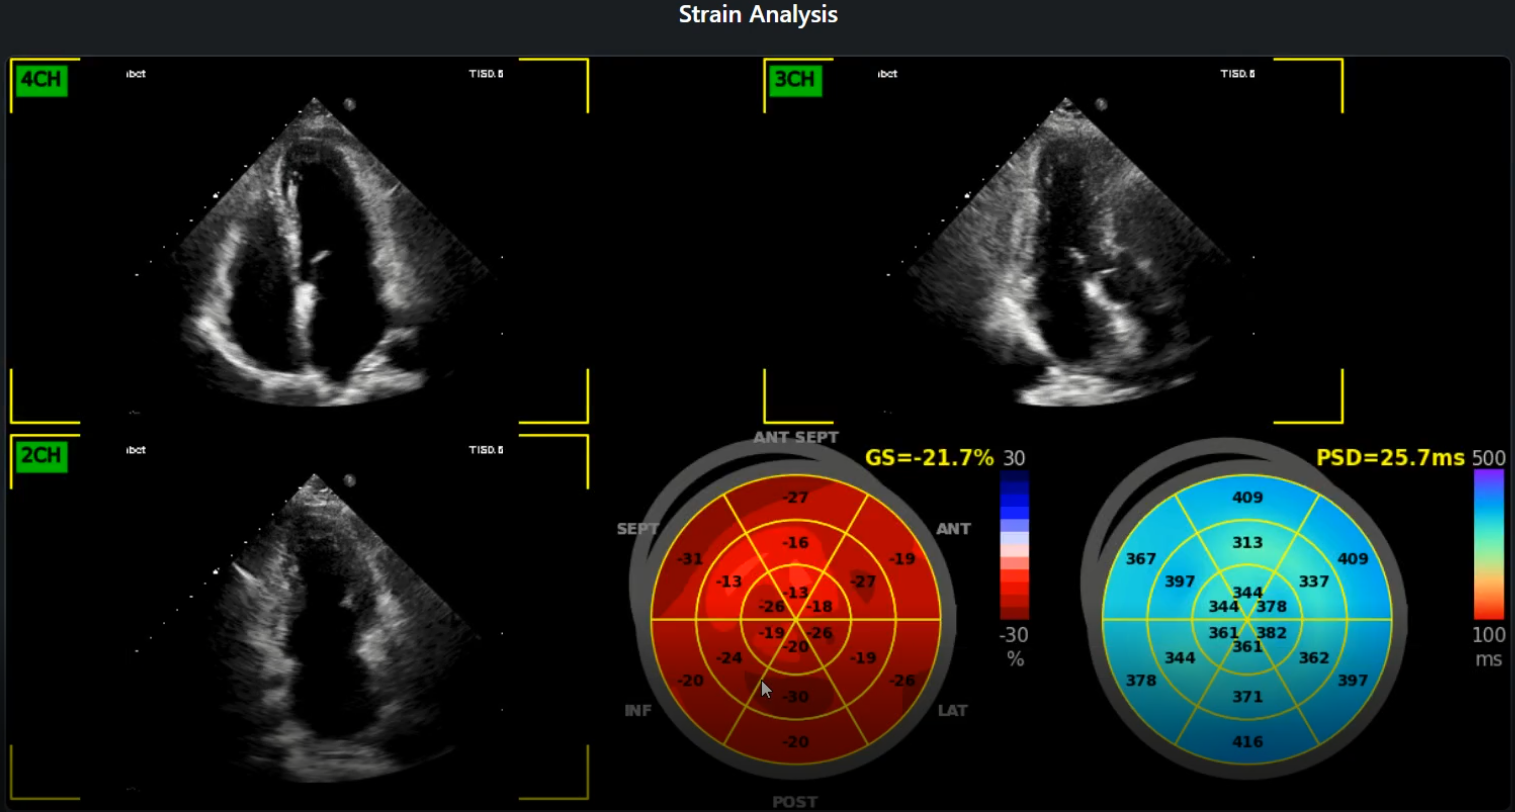

• Global Longitudinal Strain (GLS): Get accurate and reproducible GLS measurements, a key indicator of LV systolic function, aiding in early detection of cardiac dysfunction.

• Wall Motion Abnormalities: AI-assisted detection of regional wall motion abnormalities, providing critical insights for ischemic heart disease evaluation.